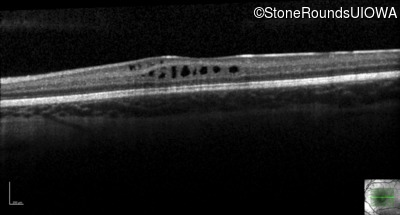

XL Retinoschisis (IIIB1)

XL Retinoschisis (IIIB1)

This 6 year old boy first experienced difficulty reading and seeing the blackboard at age 5.